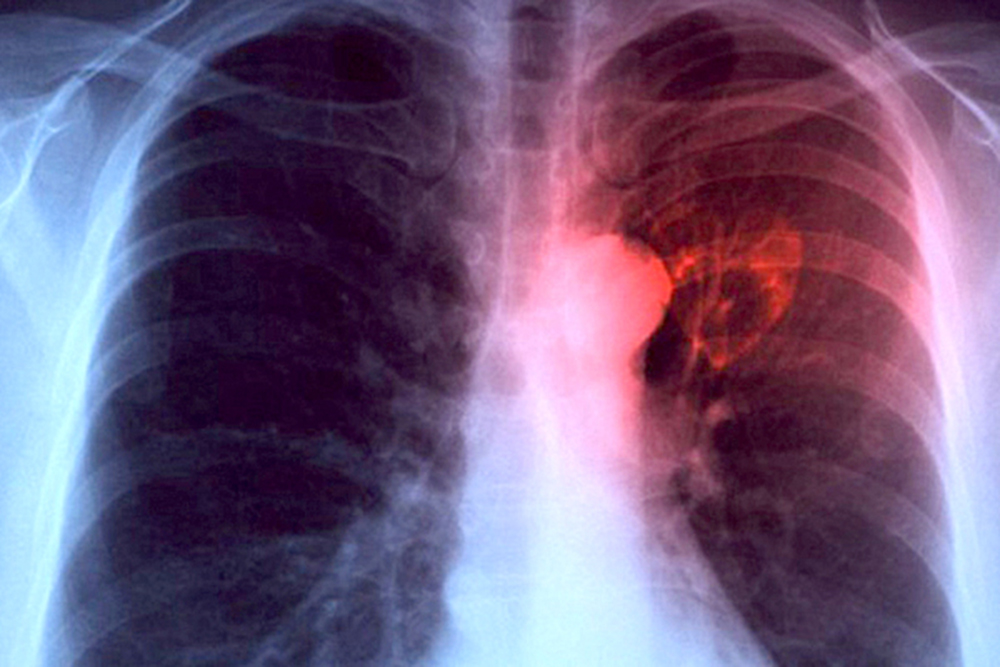

Home Guía de Salud Page 285

Guía de Salud